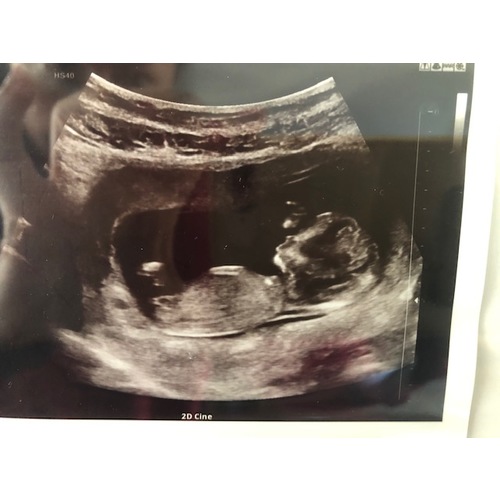

Wie durft een gokje te wagen? Ik ben benieuwd :)

Echo is van 12+4 dagen. Over 4 weekjes weet ik het!

Liefs

Meisje

Hey jij had je foto gister nog geplaatst (daar had ik op gereageerd) 馃槈